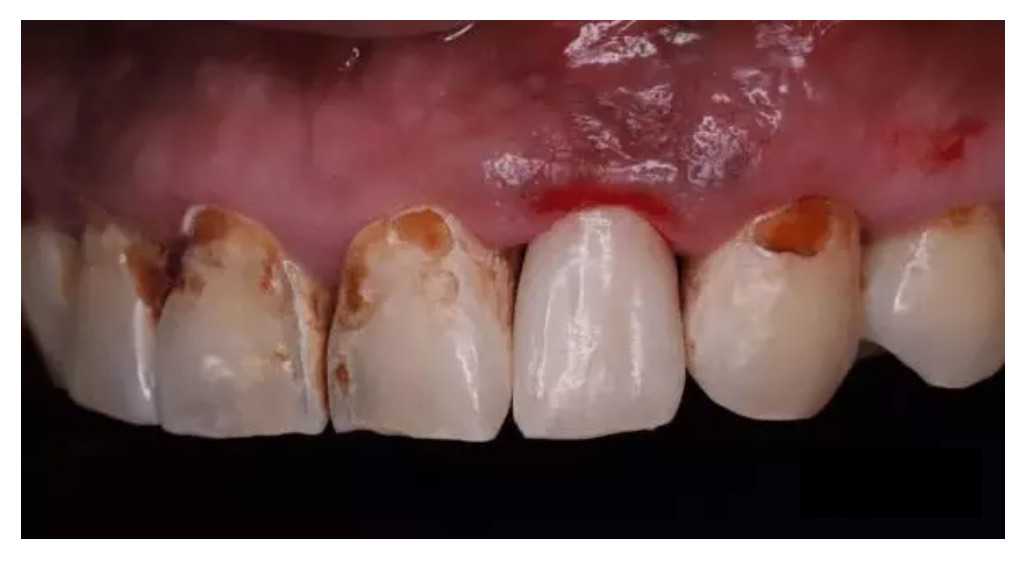

凭借着各式各样的口味、清爽的口感,碳酸饮料深受很多年轻人的喜爱。有些人喜欢在口渴时喝碳酸饮料,觉得这样非常解渴,还有些人甚至将碳酸饮料当水喝。但值得注意的是,长期喝碳酸饮料易导致牙齿软化发生龋齿,俗称“可乐牙”。

“可乐牙”是一种酸蚀症

碳酸饮料呈弱酸性,牙齿表面的主要成分是磷酸钙,长期大量喝可乐,酸性饮料会导致牙齿表面的钙质缓慢析出,这样牙齿因缺钙导致结构松软,变得脆弱和敏感,很容易被细菌侵入,诱发龋齿。